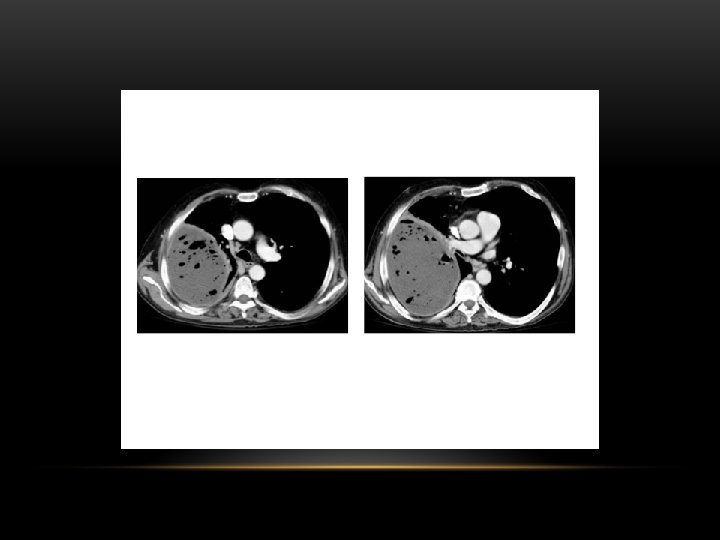

CT scan of left empyema with pleural enhancement

loculated pleural effusion